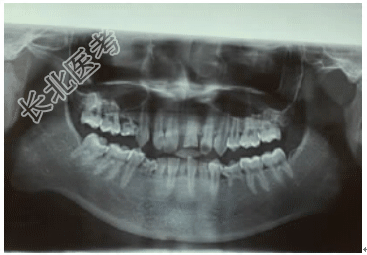

[材料题] 一般资料病例男,16岁主诉因“乳牙未替换、进食时下前牙咬上颌牙龈”就诊。现病史其母亲叙述,患者出生后乳牙萌出正常,但换牙较同龄人晚,有部分牙齿至今未替换,近日出现进食时咬上颌牙龈导致疼痛现象。患者8岁时,因跌倒致左上前牙横折,曾在外院行“根尖诱导成形术”。既往史既往体健,母乳喂养,无拔牙史及药物过敏史,否认传染病史及家族遗传病史,否认孕期接触X线照射,无重大疾病及毒物接触史。家族史独子,家族中无类似患者,父母体健,牙齿均未见异常。体格检查身高172cm,体重56kg,神志清楚,对答切题,心、肺、脊柱及四肢未见异常,毛发、汗腺等发育正常,指、趾甲正常。口腔专科检查:混合牙列,11、12、13、16、17、21、22、23、25、26、27、31、34、36、37、42、45、46、47萌出,55、73、75、81、83、84滞留。右侧磨牙中性关系,左侧磨牙远中关系,21牙冠1/2横折,色暗,叩(-),不松动;全口乳牙均有不同程度松动,上颌牙列散在间隙,下前牙舌倾,前牙深覆合Ⅲ°,深覆盖Ⅰ°;面型左右对称,侧面观呈直面型,下颌后缩,张口度及颞颌关节未见异常。辅助检查全口曲面断层片(图1)示:14、15、24、32、33、35、41、43、44未见牙胚;乳牙根部分吸收;21根尖周低密度影。